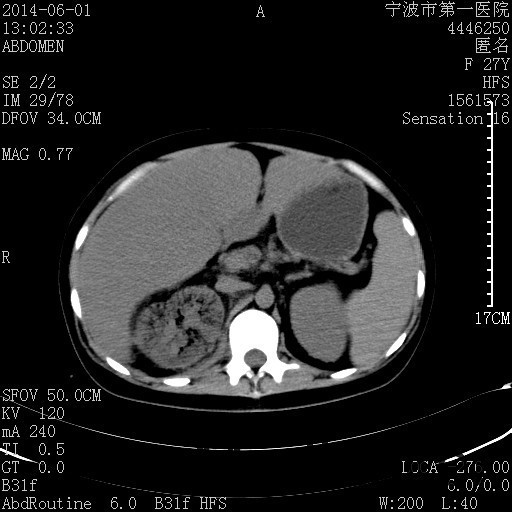

患者,女,27岁,因“右下腹疼痛伴呕吐2天”入院 患者无明显诱因出现右下腹疼痛伴呕吐、发热,体温最高39度,急诊CT示:右肾集气,考虑气性肾盂肾炎。

查体: 右肾区叩击痛,右下腹压痛,无反跳痛。 辅助检查: 空腹血糖9.7mmo/L,餐后血糖18mmol/L 血常规:白细胞 11.3*109/L, 中性百分比 77.4%, 血红蛋白 8g/L, 血小板 319*109/L 尿常规 WBC+++ 生化:白蛋白 37.5g/L,肝肾功能正常 泌尿系CT:右肾集气

诊断为“气性肾盂肾炎,感染性休克,糖尿病酮症酸中毒” 血、尿、脓液培养均示“克雷伯杆菌” 入院第2天行“右双J管置入术” 入院第3天、7天行“右肾穿刺造瘘术” 入院1月行“右肾切除术” 术后顺利康复出院。